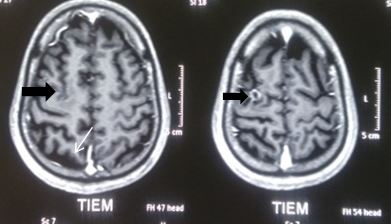

Bệnh diễn biến 1 tháng bệnh nhân có biểu hiện động kinh, đau đầu, nôn và yếu nửa người trái. Bệnh nhân được chụp cộng hưởng từ sọ não phát hiện hình ảnh u não nên được chuyển vào Trung tâm Y học hạt nhân và Ung bướu – Bệnh viện Bạch Mai để điều trị.

Hình 2: Hình ảnh MRI sọ não có khối u não di căn bán cầu phải kích thước 2 - 3cm, phù não rộng xung quanh